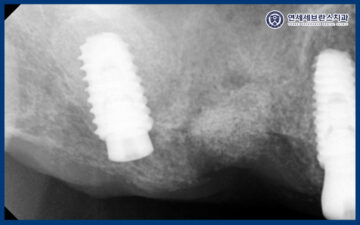

25.06.18 / 25.09.18

그리고 오른쪽 아래는

발치 후 뼈이식만 먼저 진행하여

충분한 치유와 안정화를 도모하였습니다.

이후 이식한 뼈가 잘 결합되어

임플란트 식립을 진행하였습니다.